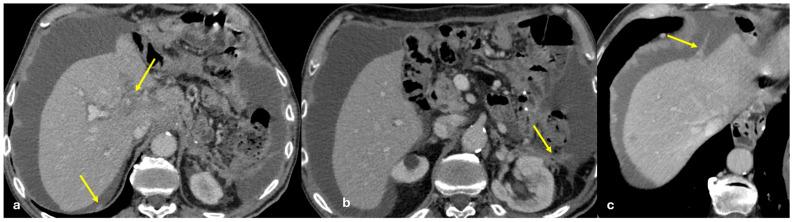

The peritoneum is a thin membrane that lines the abdominal cavity and covers the abdominal organs. It serves as a conduit for the spread of various pathological processes, including gas and fluid collections, inflammation, infections, and neoplastic conditions. Peritoneal carcinomatosis is the most common and well-known pathology involving the peritoneum, typically resulting from the dissemination of gastrointestinal and pelvic malignancies. However, numerous benign and malignant peritoneal diseases can mimic the imaging appearance of peritoneal carcinomatosis. The aim of this review is to revisit the anatomy of peritoneal compartments and elucidate the patterns of peritoneal disease spread. Emphasis is placed on identifying the distinctive imaging features of both neoplastic and non-neoplastic peritoneal diseases that differ from peritoneal carcinomatosis.

腹膜是一层薄的膜,它衬于腹腔内并覆盖腹部器官。它是各种病理过程扩散的通道,包括气体和液体聚集、炎症、感染及肿瘤性疾病。腹膜癌病是涉及腹膜的最常见且广为人知的病理情况,通常由胃肠道和盆腔恶性肿瘤的播散引起。然而,许多良性和恶性腹膜疾病可模仿腹膜癌病的影像学表现。本综述的目的是重新审视腹膜腔室的解剖结构并阐明腹膜疾病的扩散模式。重点在于识别与腹膜癌病不同的肿瘤性和非肿瘤性腹膜疾病的独特影像学特征。